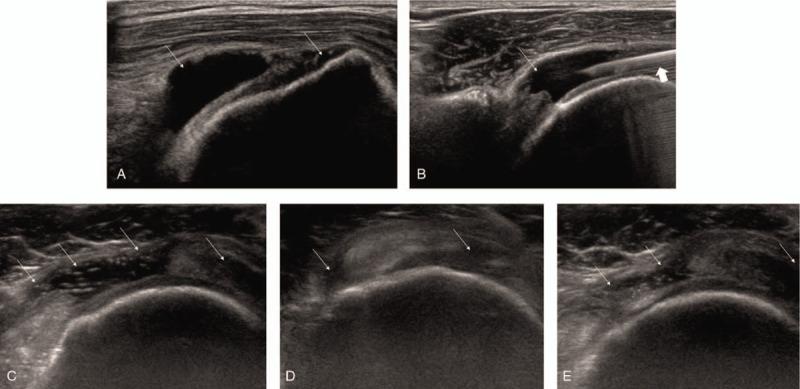

Physical examination and imaging studies revealed rotator cuff tears with remarkable quantities of fluid in the SASD bursa.

The patients underwent ultrasound (US)-guided aspiration of the bursal fluid and intra-articular corticosteroid injection, following which, all patients experienced reduced shoulder pain for several months.

体格检查和影像学研究显示肩袖撕裂且SASD滑囊内有大量液体。

患者接受了超声(US)引导下的滑囊液抽吸和关节内皮质类固醇注射,之后所有患者肩部疼痛均减轻了数月。